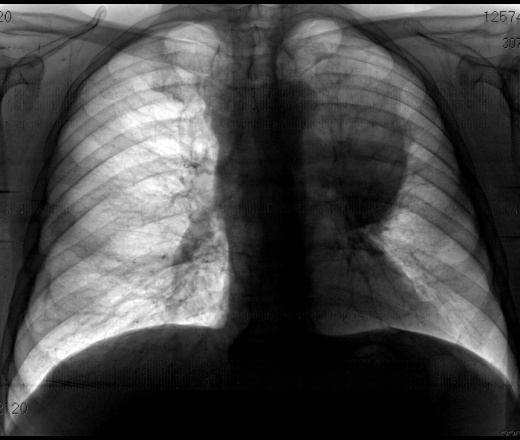

Фиброз Легких На Рентгене Фото

Фиброз Легких На Рентгене Фото 115 фотографий